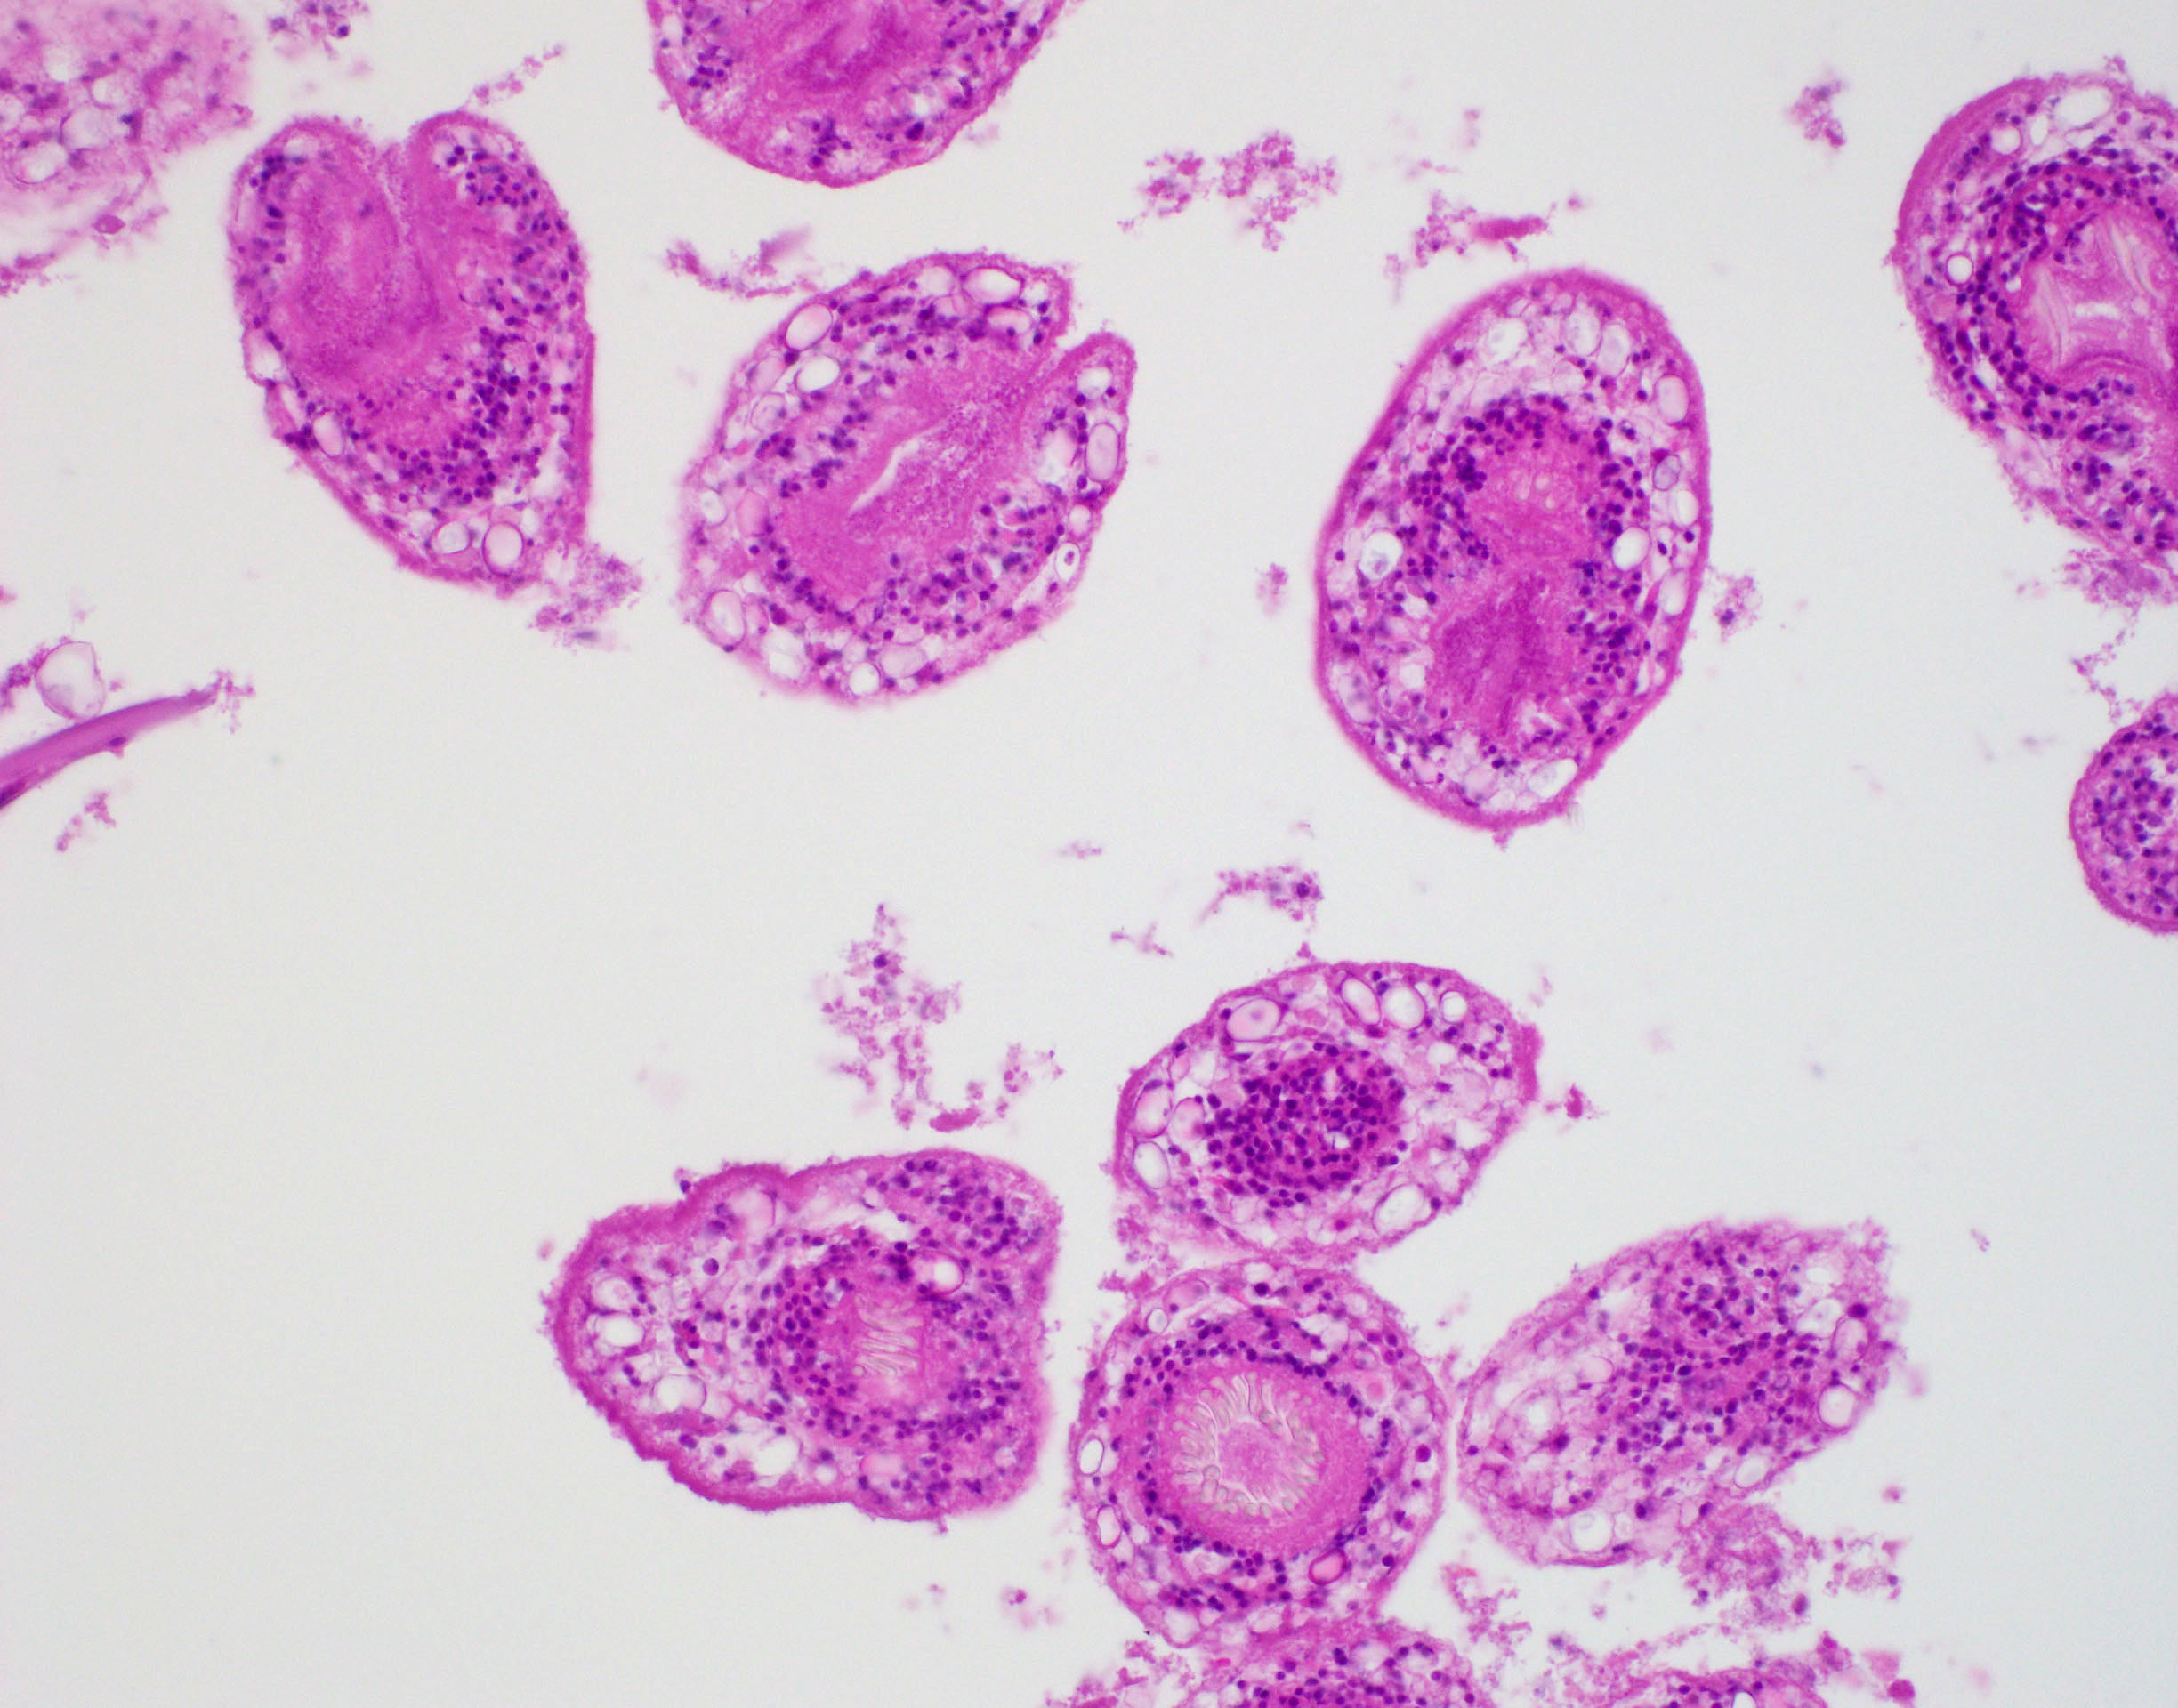

Microscopic (histologic) description

- E. granulosus

- Cyst wall has 3 structural components:

- Outer acellular laminated membrane (1 mm thick)

- Germinal membrane (a transparent nucleated lining)

- Protoscolices, attached to the membrane and budding from it

- Protoscolices are ovoid and contain hooklets (birefringent under polarized light) and a sucker

- Outer fibrotic layer with granulation tissue with increased eosinophils also exists

Microscopic (histologic) images

- Comment: There are degenerated echinococcal cysts that contain abundant debris with protoscolices fragments.